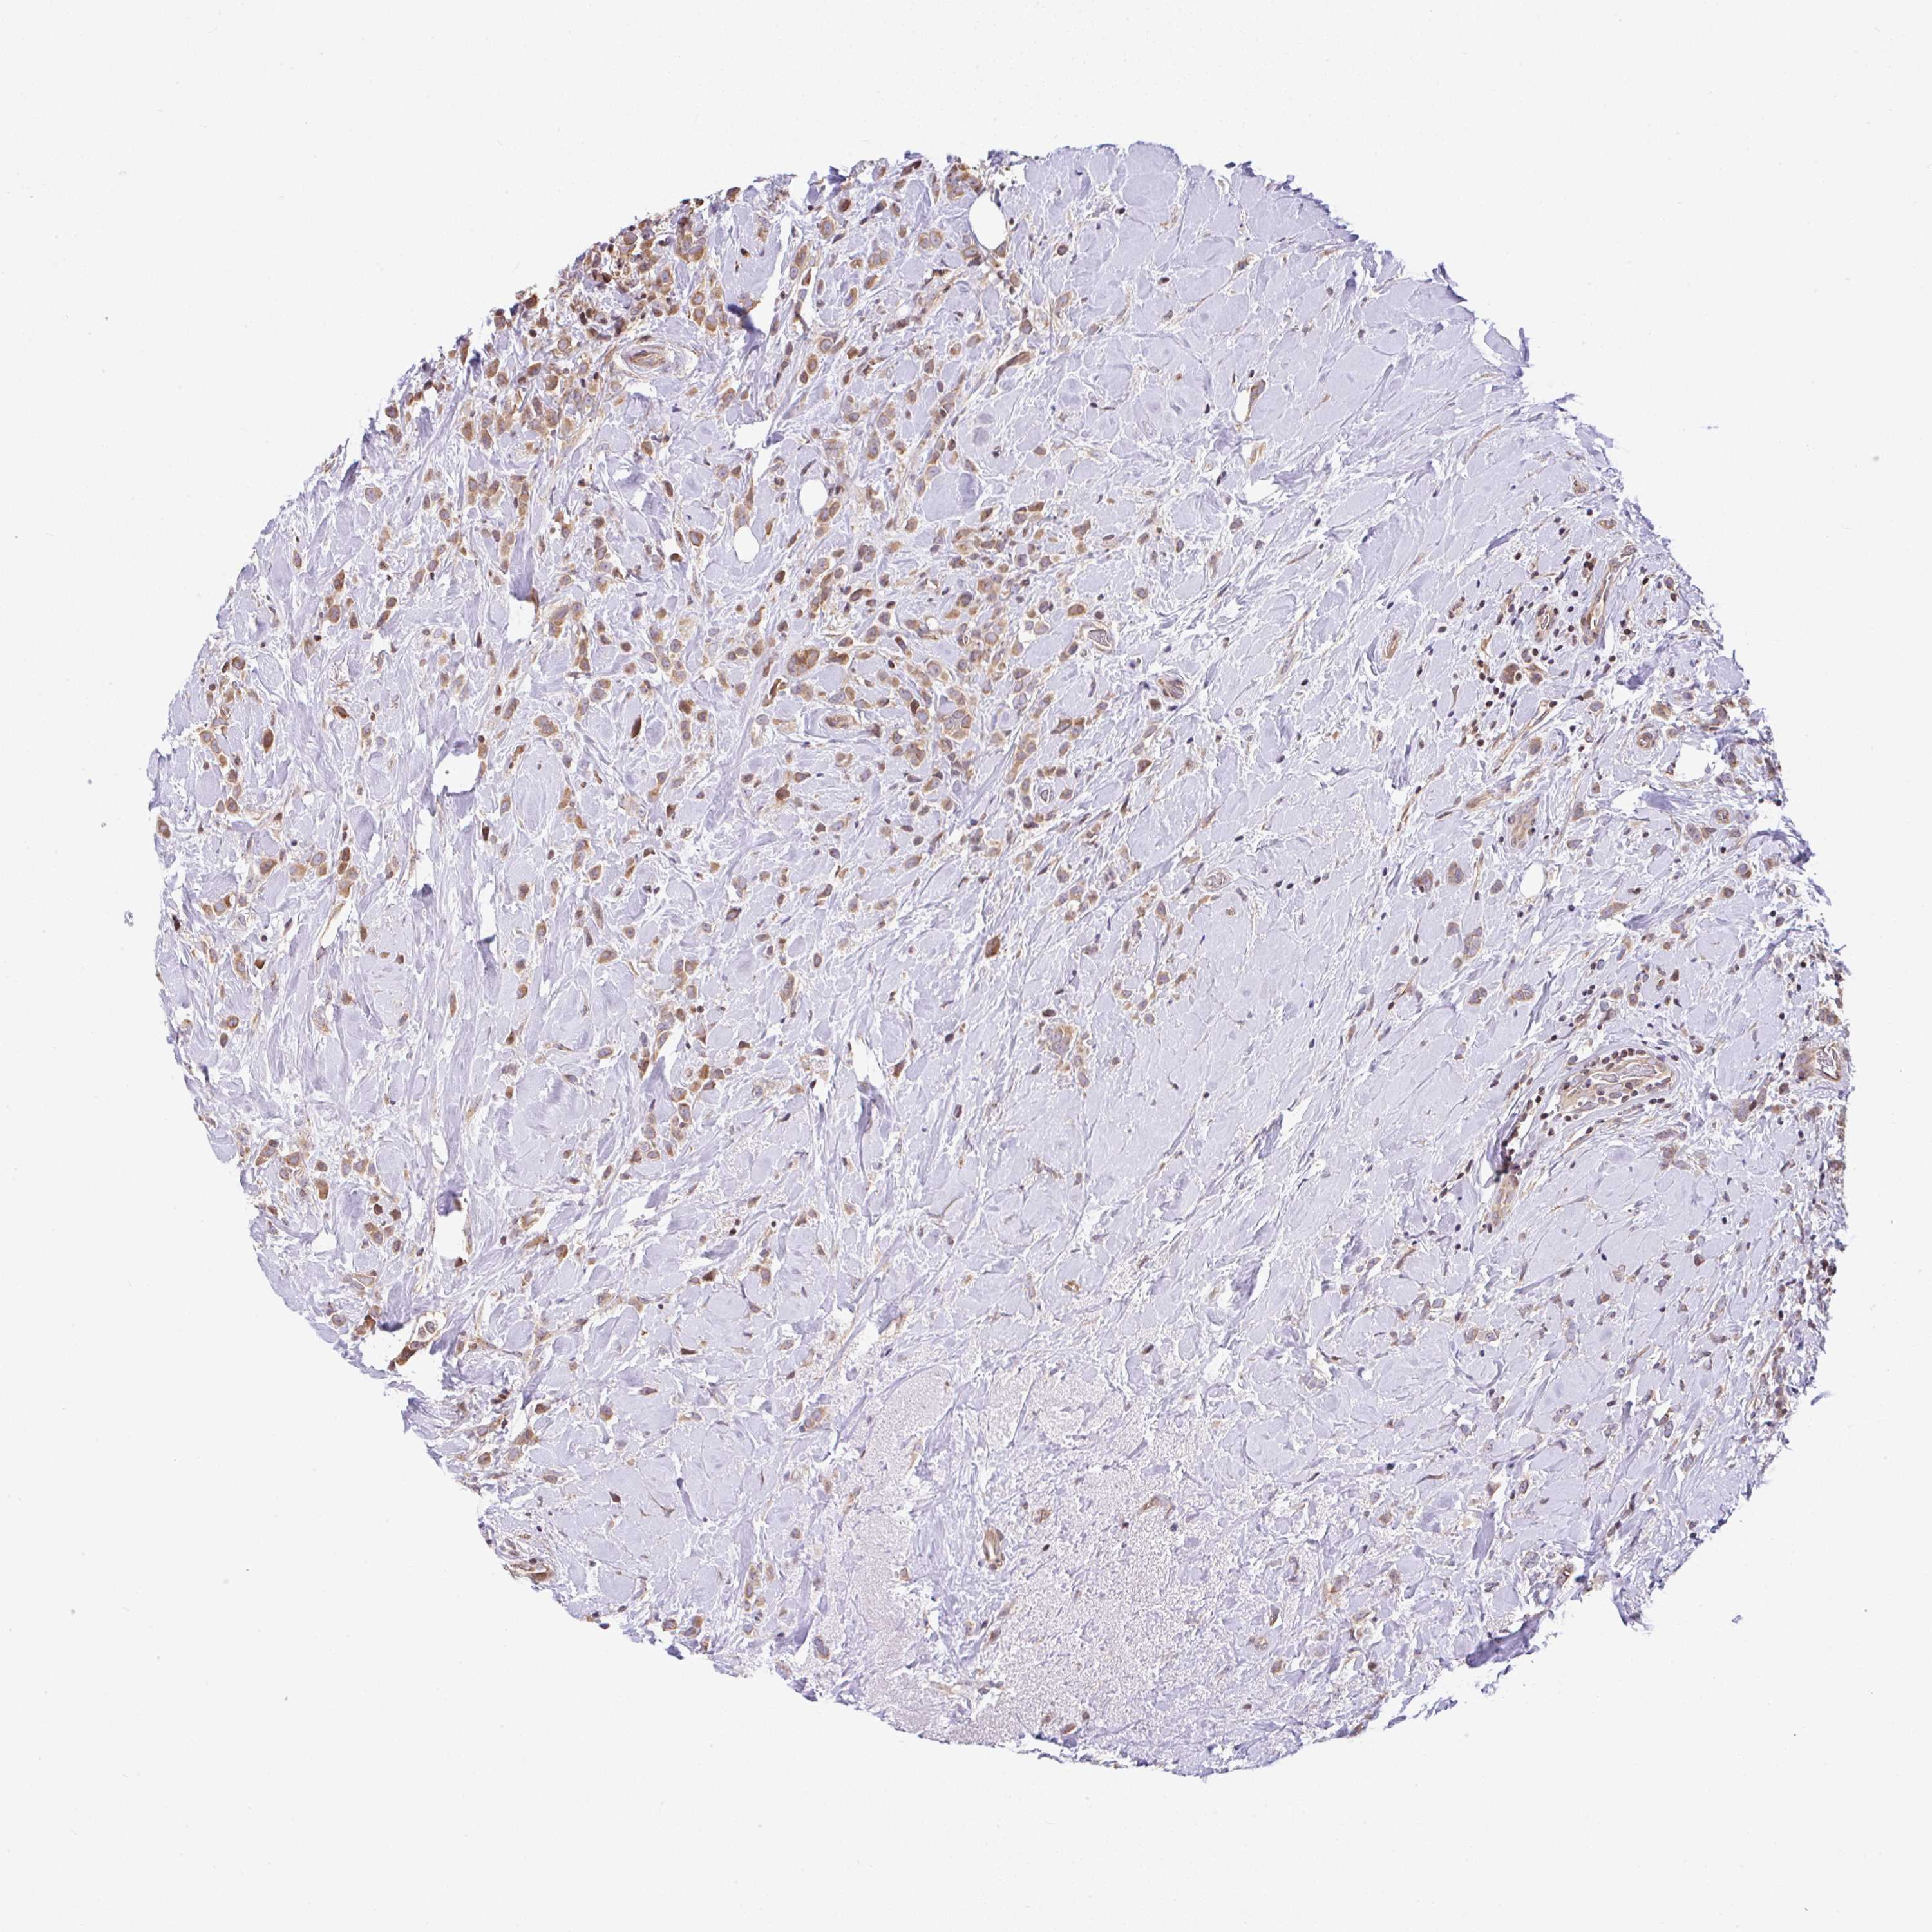

BRCA TCGA BRCA VALIDATION PROTEIN EXPRESSION